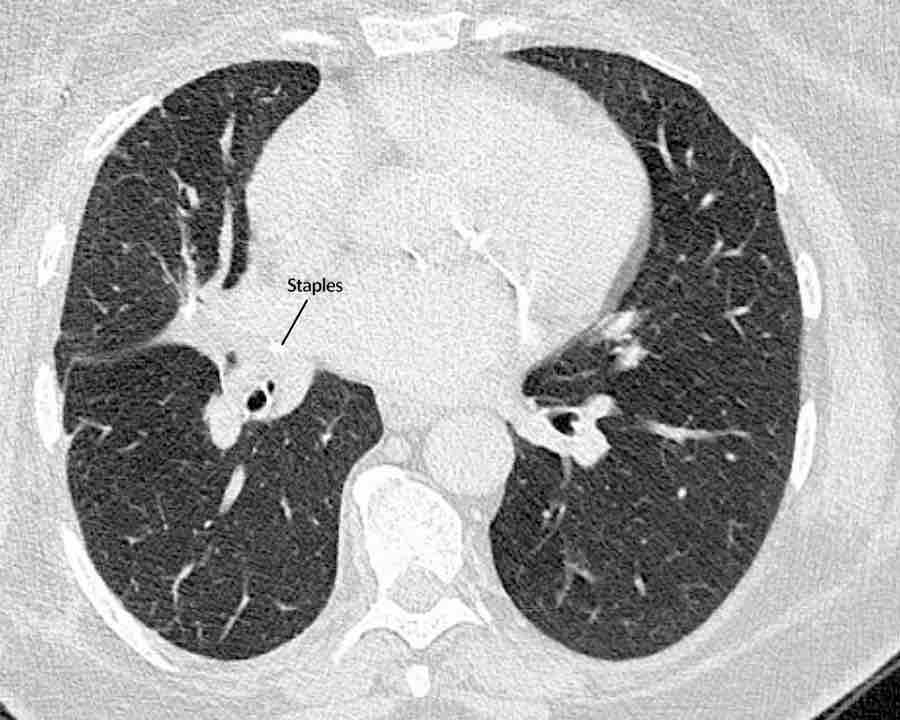

Cắt thùy và cắt phân thùy phổi

Để cắt bỏ các tổn thương khu trú, phẫu thuật viên có thể lựa chọn giữa cắt hình nêm không theo giải phẫu, cắt phân thùy theo giải phẫu, cắt (một hoặc hai) thùy phổi hoặc cắt toàn bộ một phổi.

Theo dõi đường đi của các phế quản đến đường khâu ghim sẽ giúp xác định phương pháp phẫu thuật đã thực hiện và phần phổi đã được cắt bỏ.

Hình ảnh

Cuộn qua các hình ảnh.

Phế quản thùy trên, phế quản trung gian và phế quản thùy dưới tiếp tục đi về phía ngoại vi.

Phế quản thùy giữa kết thúc tại vị trí đặt các ghim phẫu thuật.